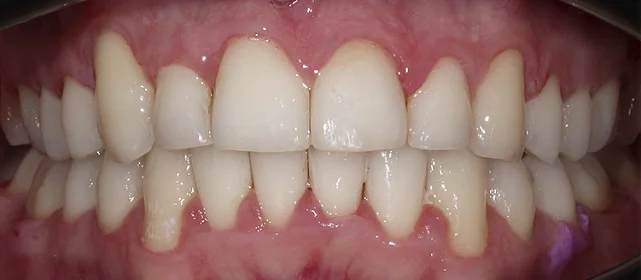

Обе челюсти сужены — зубам не хватало места, они стояли скученно на верхней и нижней челюсти. Нарушена кривая смыкания — жевательные зубы были на разной высоте.

Зубы выровнены, скученность устранена, линия смыкания нормализована. Установлены несъёмные ретейнеры на обе челюсти, сняты слепки для ретенционных кап.

Проблема: Пациентка живёт за рубежом и обратилась с жалобами на неровные зубы. При осмотре обнаружили сужение обеих челюстей, скученность на верхней и нижней, а также деформацию кривой смыкания — жевательные зубы стояли на разной высоте, из-за чего нагрузка при еде распределялась неравномерно. Дополнительная сложность — пациентка не могла приезжать на визиты часто.

Решение: Поставили элайнеры Click на обе челюсти. Начали с 32 кап, но случай потребовал три дозаказа: 30, 10 и 10 кап — итого 82 капы за 30 месяцев. Количество дозаказов объясняется и сложностью случая (скученность плюс деформация кривой Шпее), и тем, что контрольные визиты были реже обычного из-за проживания за границей. Тем не менее результат достигнут: зубы ровные, смыкание в норме. На ретенцию пациентка приехала отдельно — зафиксировали ретейнеры на обе челюсти, сняли слепки для ретенционных кап.